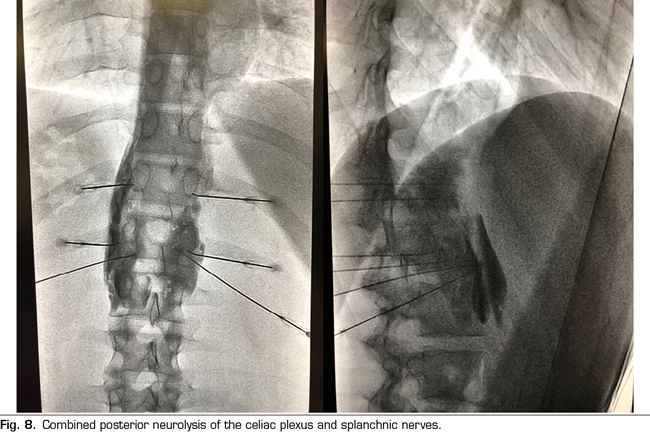

Following the conclusions of the previously described publications, an interventional treatment algorithm for patients with visceral pain associated with pancreatic cancer can be established (Figure 7). The standard procedure would be the posterior approach of the celiac plexus (classical approach), since today it continues being the one with the greatest scientific evidence, preferably transcrural and guided by fluoroscopy, due to its simplicity and speed. Ultrasound endoscopy would be indicated for neurolysis taking advantage of its diagnostic or therapeutic indication, for situations of inability to prone position, and as an alternative in case the posterior approach fails. Percutaneous ultrasound neurolysis would be reserved for selected cases, depending on the experience of the operator, since it is the technique that has fewer publications to date. We hope that in the future, studies allowing ultrasound-guided techniques, whether percutaneous or endoscopic ultrasound, will be published as the “reference method”, since they allow the visualization of surrounding structures with real-time injection control. An alternative to the blockage of the celiac plexus is the conventional radiofrequency of the splanchnic nerves, indicated when there is tumor infiltration of the celiac trunk, important anatomical alterations or if the celiac plexus neurolysis fails. It is also possible to consider a combined neurolysis - neurolytic blockade of the celiac plexus associated with neurolytic block or radiofrequency of the splanchnic nerves -, as reflected in the study of Marra et al. (60), and as we have been performing in our usual clinical practice at HM hospitals, with the aim of increasing the success rate and duration of analgesia without increasing the incidence of complications. However, no enough comparative studies supporting this hypothesis are available so far (Figure 8).